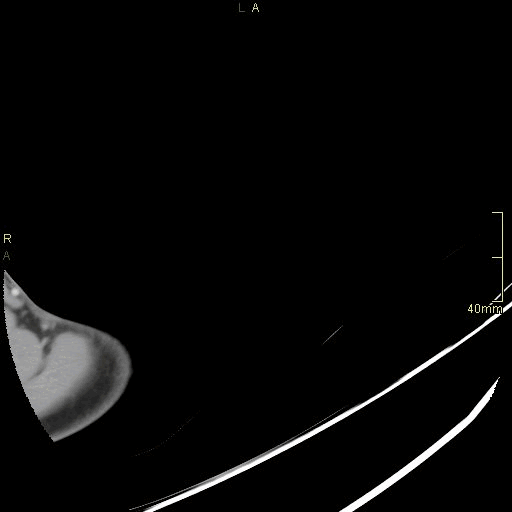

CT Humerus Contrast- Soft tissue window (axial)

CT Humerus Contrast- Bone window (axial)